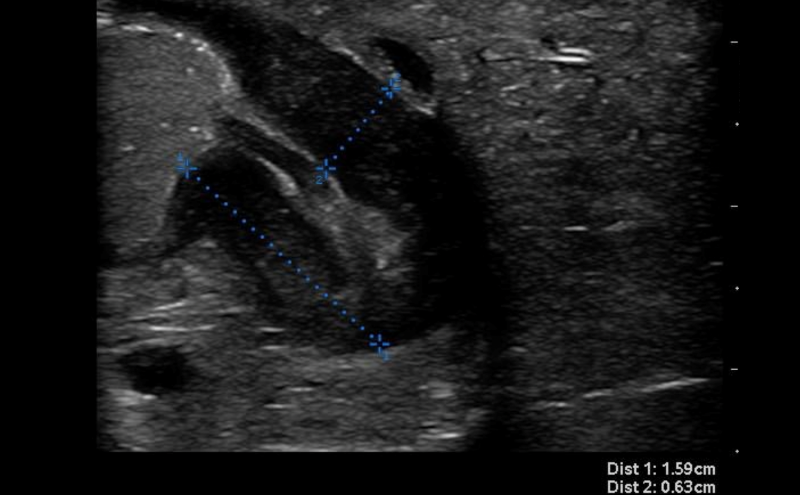

- Thickness of the pyloric muscle can be measured in the long or short axis view

- Figure 6. Hypertrophied pyloric muscle in long axis measuring 4.3mm

- A thickness of ³3mm is considered abnormal or hypertrophied

- Some experts also advocate the measurement of pyloric channel length. Unfortunately, there is no agreement for a firm cutoff for normal. In general, anything over 18mm should be considered abnormal.